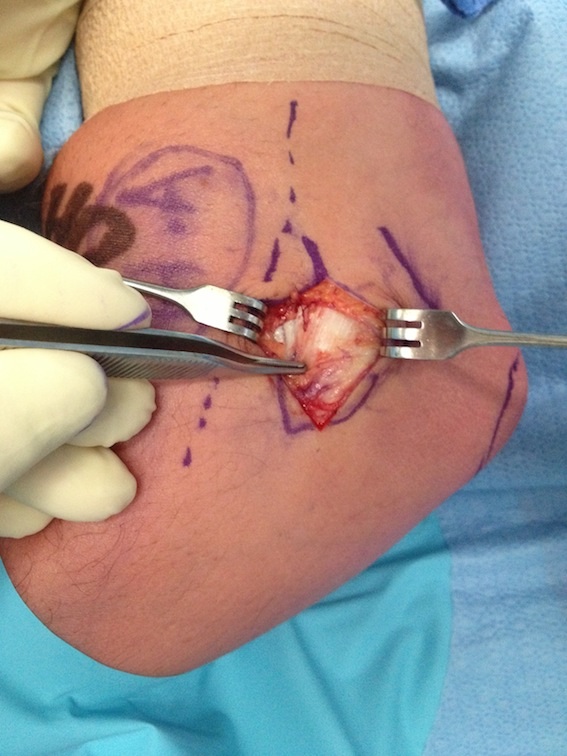

Open tennis elbow release

Technique

Incision centered on common extensor origin

- slightly anterior to radiocapitellar joint

- elevate ECRL (ECRL muscular at this point)

- ECRB is deep and posterior to ECRL

- detach ECRB from lateral epicondyle

- debride degenerative tissue and decorticate underlying common extensor origin

- +/- reattach ECRB with suture anchors

Post tennis elbow repair with anchor